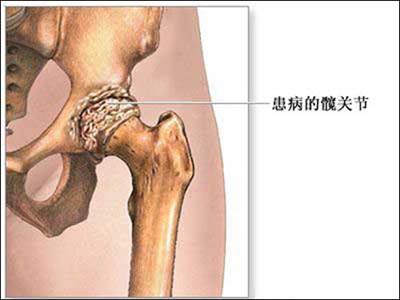

髋关节骨关节炎

图片尺寸400x300